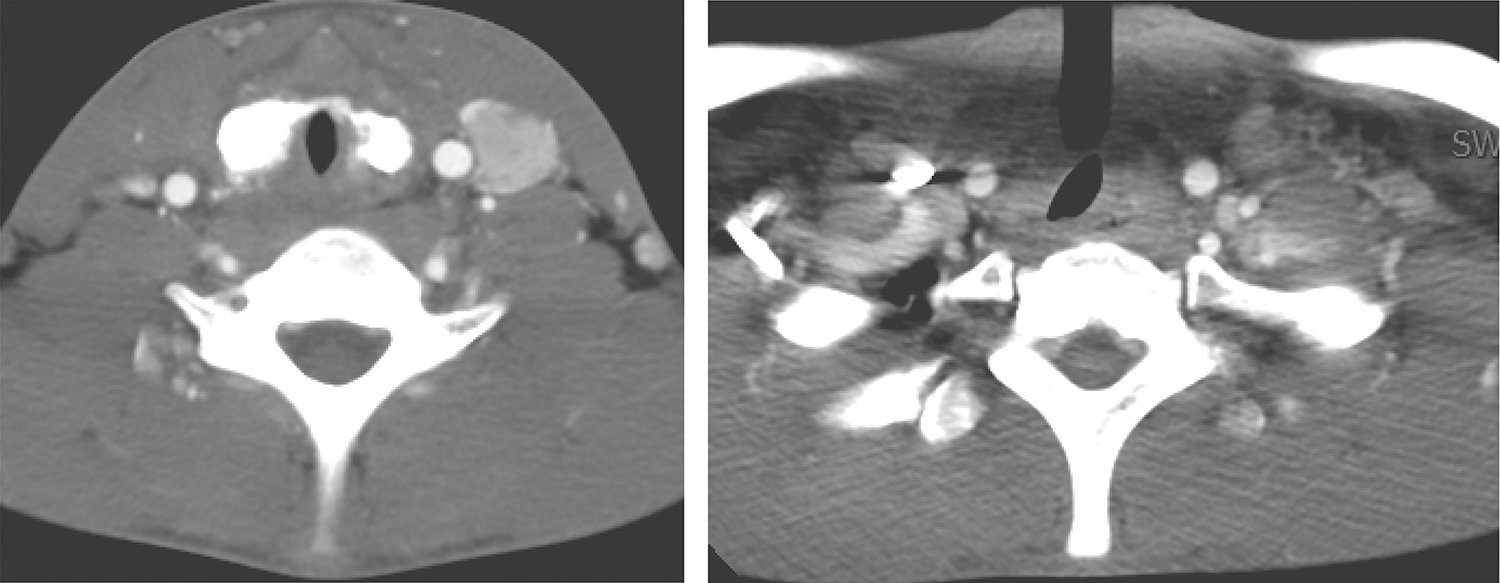

2.2014年6月24日颈胸部CT

甲状腺形态大部分失常、边缘部分毛糙,其周围可见边界不清低密度影(与相邻肌肉密度相仿),与食管分界欠清楚,气管受压变窄(可见气管插管影)(图2)。

图2 颈部增强CT示甲状腺周围边界不清低密度影,气管受压

双侧颈深组、锁骨上及双侧气管食管沟多发肿大淋巴结,较明显强化(图3),大者短径约1.5cm。

图3 颈部增强CT示双侧颈多发肿大淋巴结